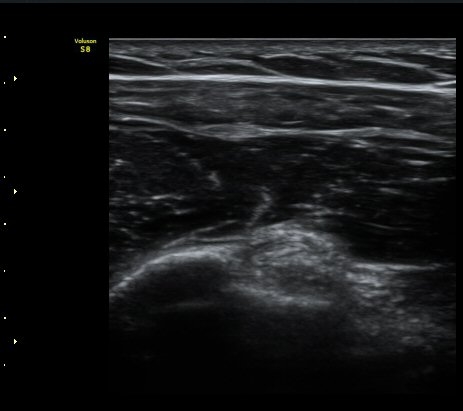

°ß°©ÇÏ±Ù°Ç Á¾´Ü¸é°Ë»ç¿¡¼­ ƯÀÌ ¼Ò°ß ¾øÀ½

(no specific abnormal findngs with longitudinal scan of subscapularis tendon) »çÁø 3